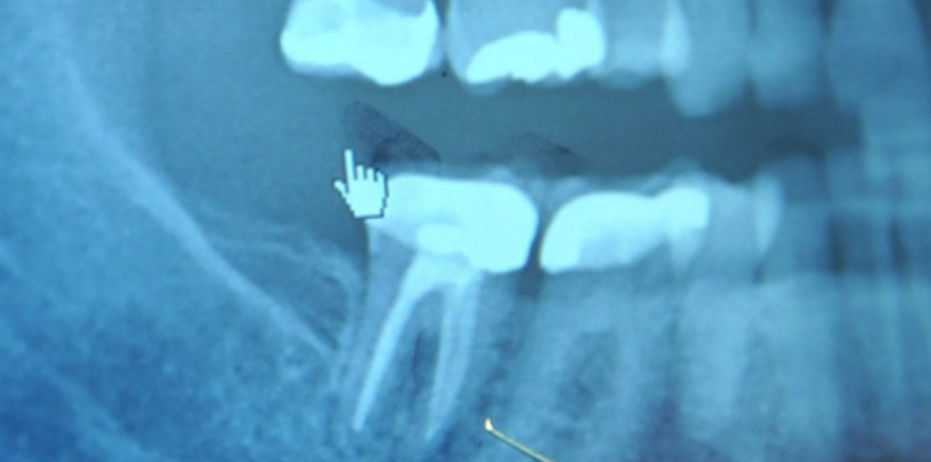

Say goodbye to dark, unsightly fillings and hello to a brighter, healthier smile! White fillings are a modern, mercury-free alternative to traditional silver (amalgam) fillings. Not only do they offer excellent bond strength and durability comparable to metal fillings, but they also enhance the aesthetics of your teeth. Whether you’re dealing with a leaky metal filling or simply want a more natural look, replacing old amalgam fillings with white fillings is a safe and effective solution.